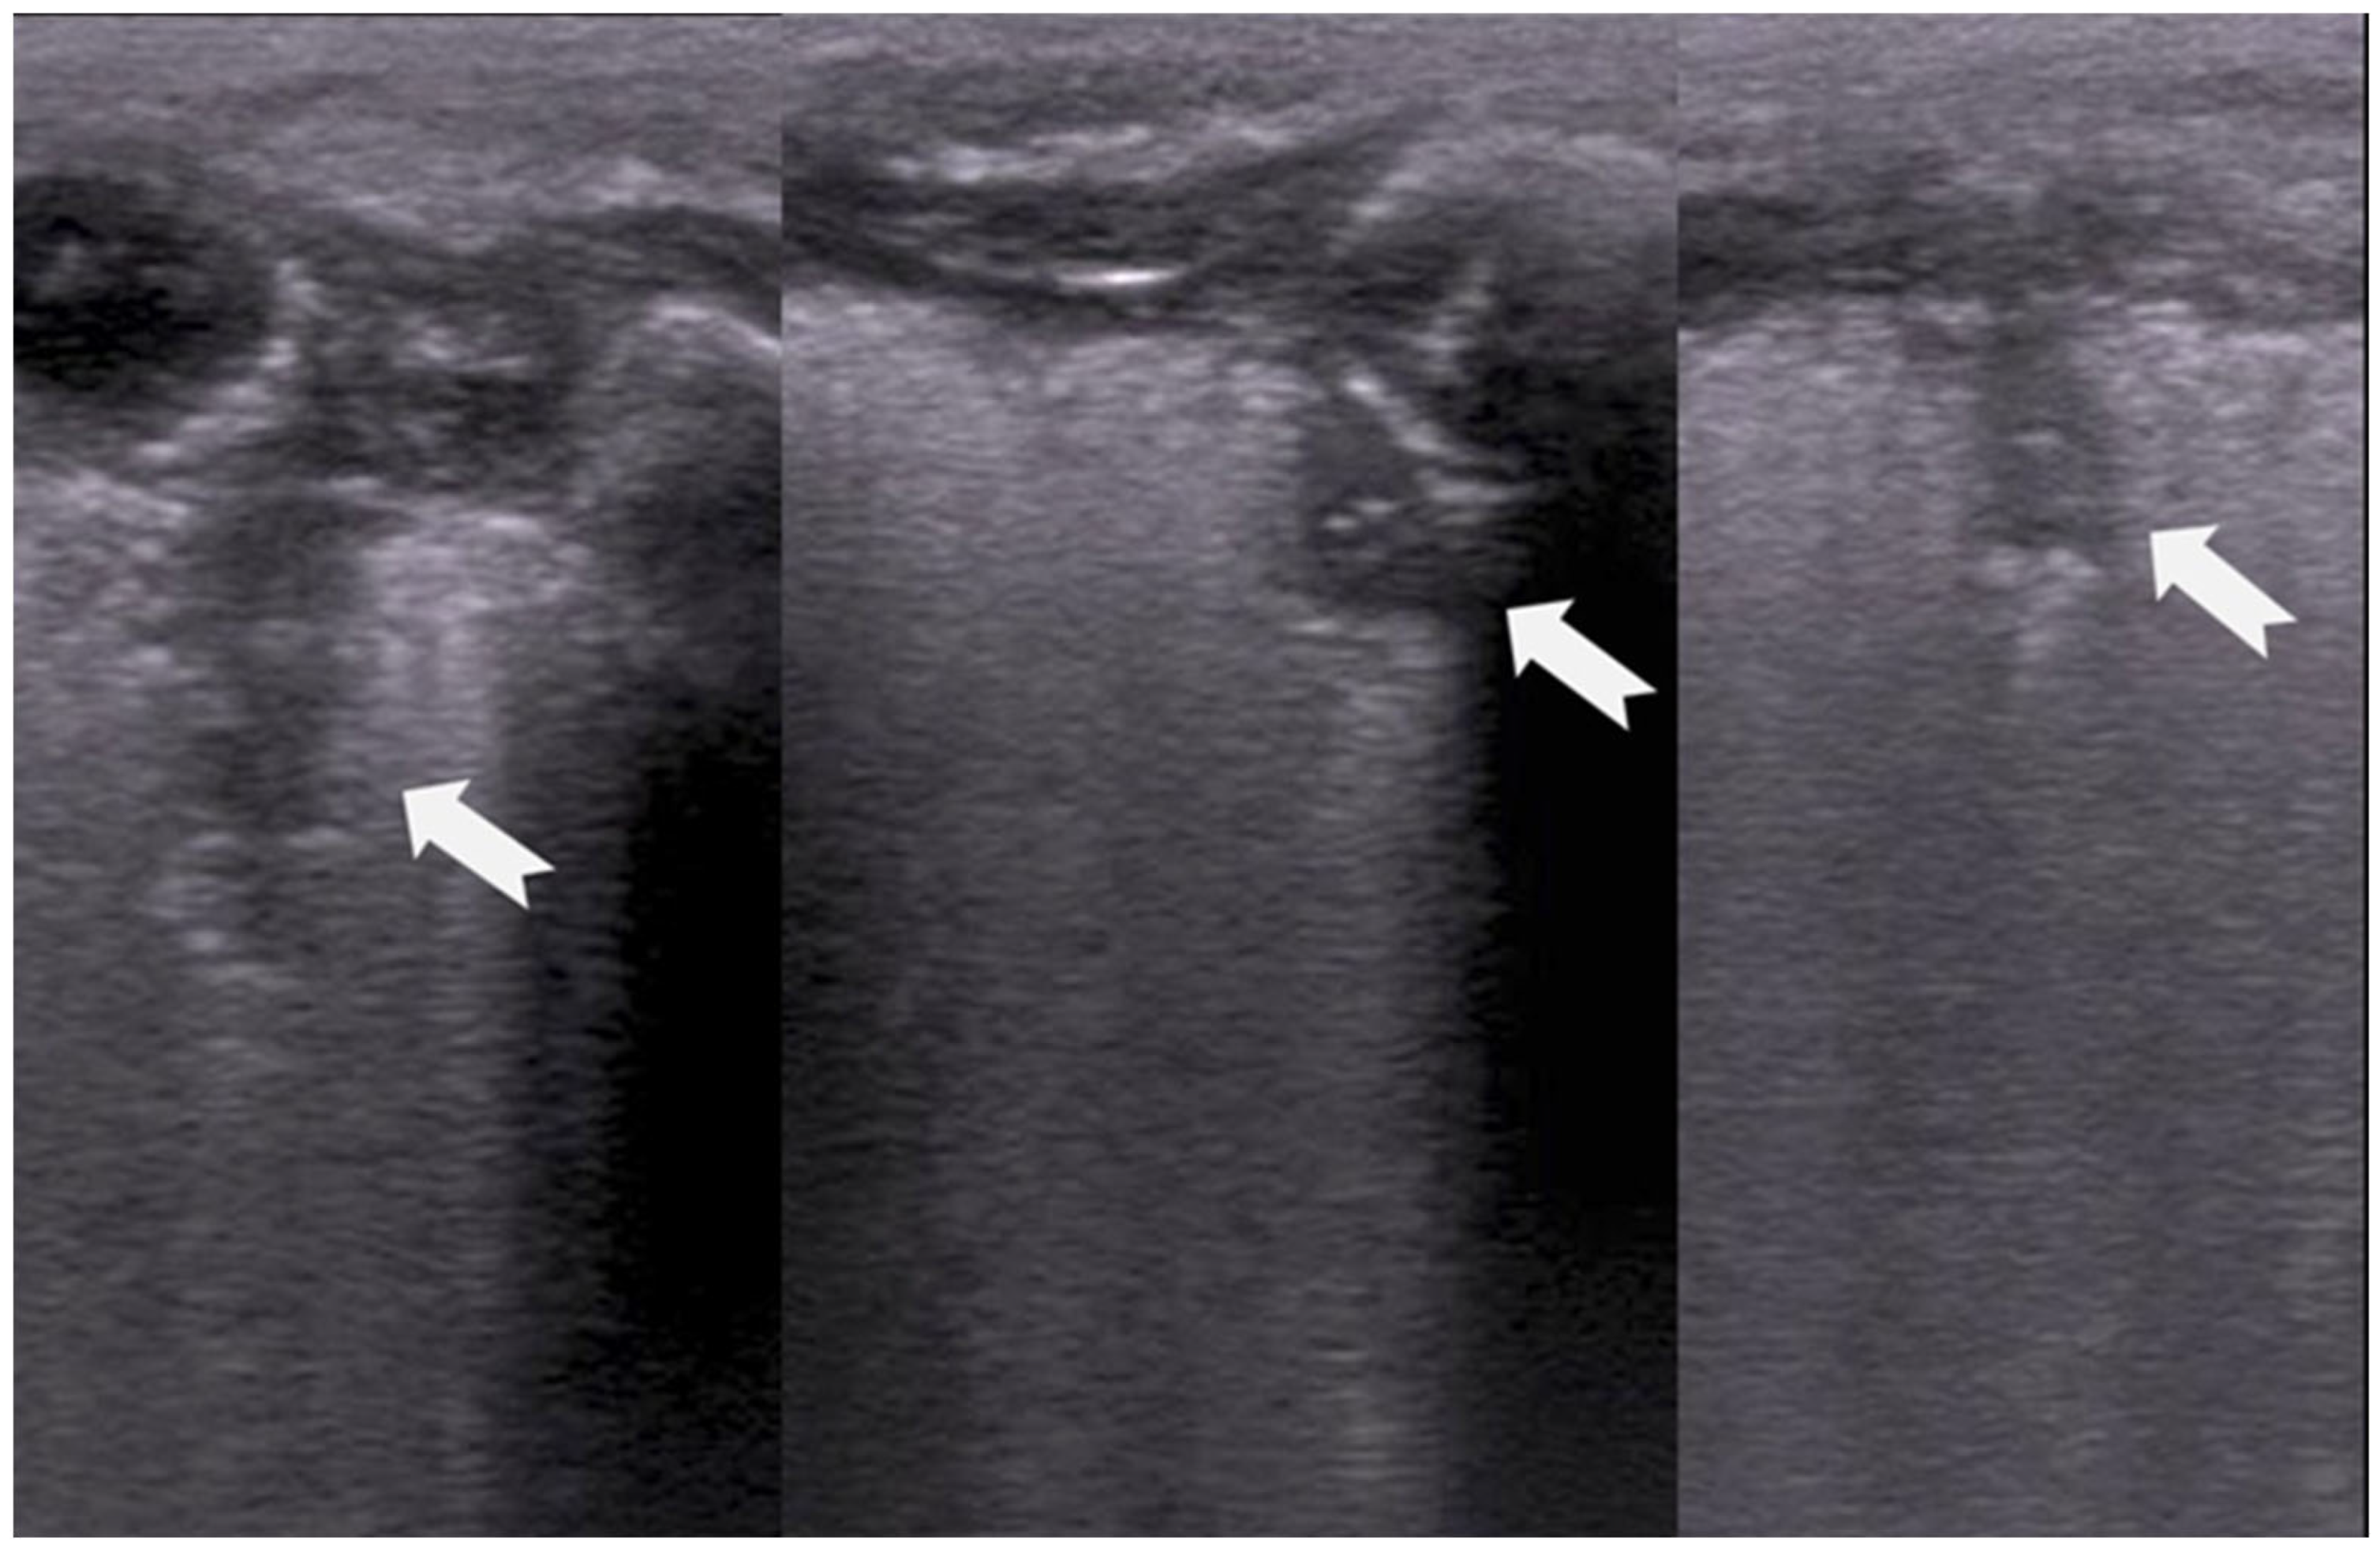

3.1.7. Lung Point Sign

3.1.8. Double-Lung-Point Sign